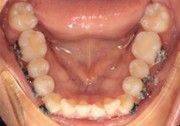

The right side shows a wide, clean bend with no distortion and minimal extra wire while bending with the IOS Mini Cinch Back Plier.

Both sides exhibit ideal bends when bent with the IOS Mini Cinch Back Plier.